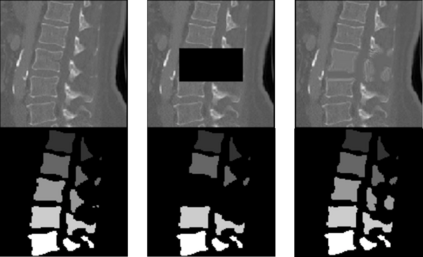

Symptomatic spinal vertebral compression fractures (VCFs) often require osteoplasty treatment. A cement-like material is injected into the bone to stabilize the fracture, restore the vertebral body height and alleviate pain. Leakage is a common complication and may occur due to too much cement being injected. In this work, we propose an automated patient-specific framework that can allow physicians to calculate an upper bound of cement for the injection and estimate the optimal outcome of osteoplasty. The framework uses the patient CT scan and the fractured vertebra label to build a virtual healthy spine using a high-level approach. Firstly, the fractured spine is segmented with a three-step Convolution Neural Network (CNN) architecture. Next, a per-vertebra rigid registration to a healthy spine atlas restores its curvature. Finally, a GAN-based inpainting approach replaces the fractured vertebra with an estimation of its original shape. Based on this outcome, we then estimate the maximum amount of bone cement for injection. We evaluate our framework by comparing the virtual vertebrae volumes of ten patients to their healthy equivalent and report an average error of 3.88$\pm$7.63\%. The presented pipeline offers a first approach to a personalized automatic high-level framework for planning osteoplasty procedures.